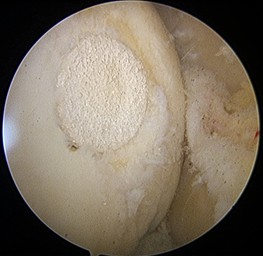

方啟榮醫師指出,隨著再生醫學與生物材料技術的進步,近年來出現了一次性微創軟骨修復手術,利用單次的關節鏡手術在受損區域同時進行清創與修補,透過特殊的載體及酵素作用,幫助關節內自行生成新軟骨。整個手術過程僅需小小的關節鏡切口,不僅減少手術次數,也降低感染風險與疼痛感。

方啟榮醫師表示,更令人振奮的是,術後兩年的影像追蹤顯示她的軟骨組織在缺損部位已再生並覆蓋良好,臨床上不僅疼痛消失,關節穩定度與活動度也大幅改善。對一位年輕、仍需長期使用膝蓋的女性來說,這樣的結果不只是醫學上的成功,更是生活品質的重生。